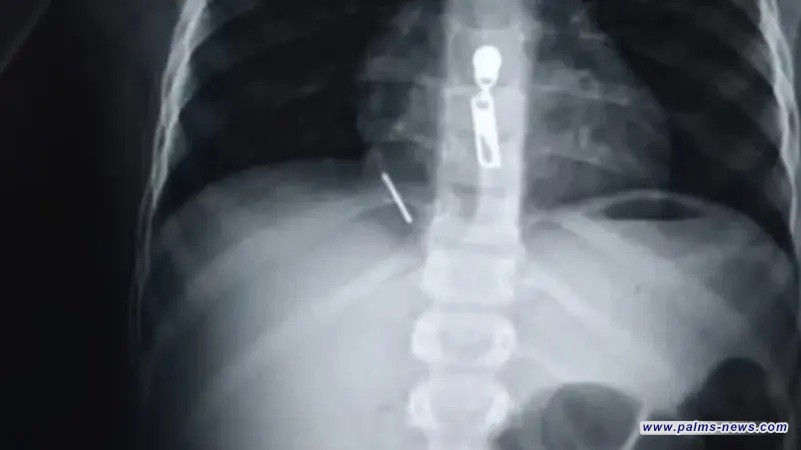

أنقذ فريق طبي بمستشفى القصر العيني في محافظة القاهرة، طفلاً يبلغ 11 عاماً، بعد ابتلاعه مسماراً بطول 5 سنتيمترات اخترق رئته ووصل إلى عضلة القلب.

بدوره، قال قائد الفريق الجراحي، حسام فتحي، إن الحالة شكلت تحدياً استثنائياً بسبب دقة الإصابة، حيث اخترق المسمار الرئة ووصل إلى عضلة القلب، مسبباً نزيفاً حول القلب استلزم تدخلاً فورياً.